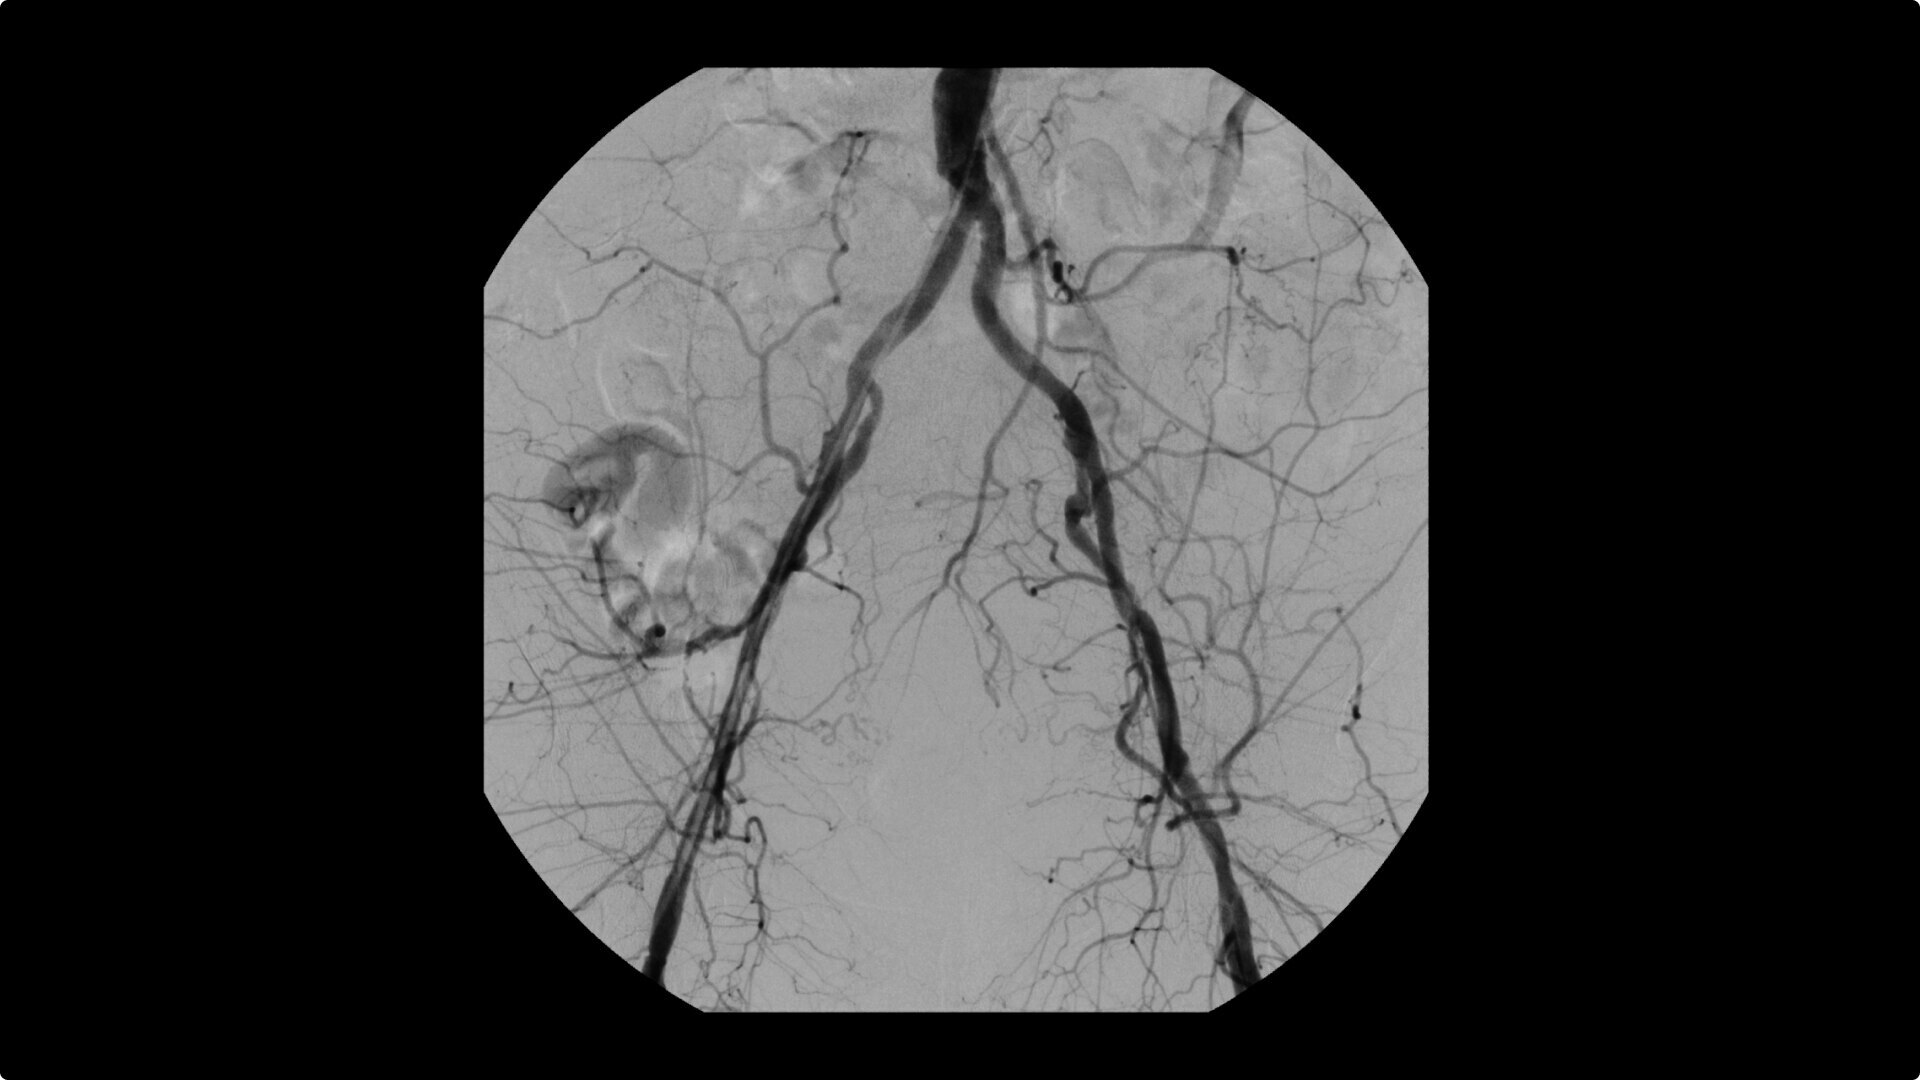

OEC C-arms are used by interventionalists and surgeons to obtain vascular imaging during peripheral to contrast run-off procedures. Superb resolution, even in the presence of motion, enables easy identification of anatomical landmarks and the extremity of the catheter, even as catheter tip moves.

Perform a full leg Bolus Chase in one contrast run with a Preset Profile that includes Motion Tolerant Subtraction, that dynamically adjusts image quality based on presence of motion.

During contrast run-off procedures, easily select contrast type with positive (e.g. Iodine) or negative (e.g. Carbon Dioxide) during subtraction. The OEC Elite CFD cardiovascular package also includes Roadmapping.

Complex vascular procedures require powerful imaging systems. OEC premium C-arms perform in a variety of procedures such as:

•Abdominal aortic aneurysm (AAA) stent and balloon deployment

• Recanalization and stent placement in iliac arteries